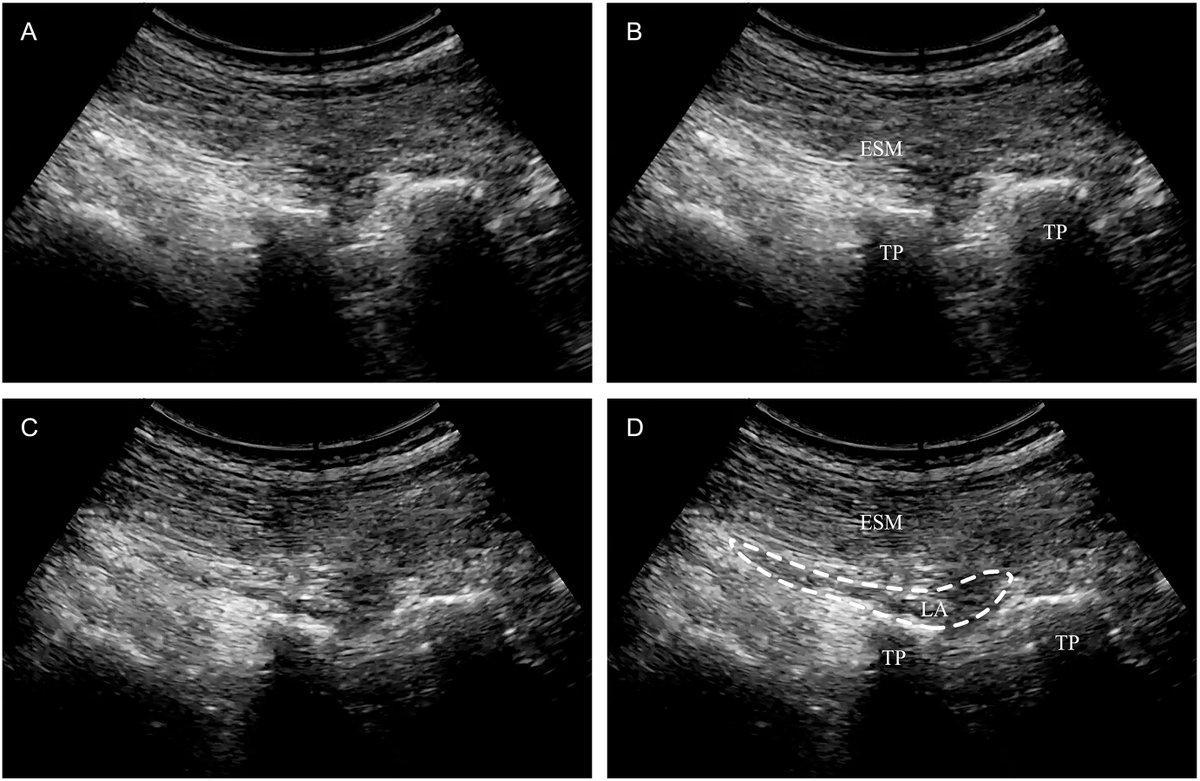

@deepak_neuro @JournalofClinAn @SNACCNeuro @naccsuk @cas_neuro @AlanaFlex @AndrewKofke @ASRA_Society @ESRA_Society @NaveenEipe @EMARIANOMD @NarouzeMD Great stuff. Wish our IRB allowed sham blocks for prospective studies given multiple meta-analysis demonstrating efficacy of ESP blocks for lumbar fusion. Curious about efficacy at 24hrs.

English

Bilateral ultrasound-guided erector spinae plane block for lumbar spinal fusion: A randomized controlled trial @JournalofClinAn

⬇️pain scores at rest 4, 8 & 12 hours post-op

⬇️pain scores on movement at 4 h post-op

⬇️opioid requirement 12 h post-op

sciencedirect.com/science/articl…